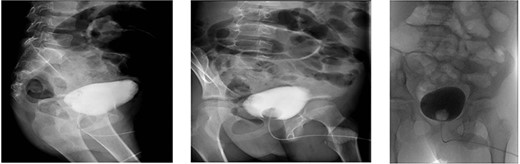

A contrast cystogram was performed on postoperative day 9, and a pelvic scan showed no leak or extravasation of the contrast fluid (Fig. 3). The catheter was removed, and the patient was discharged after successful micturition trials. Follow-up examinations performed 2 weeks and 1 month post-discharge were unremarkable and the patient presented no complaints.

Cystogram performed on postoperative day 8 showed no extravasation of the contrast material.